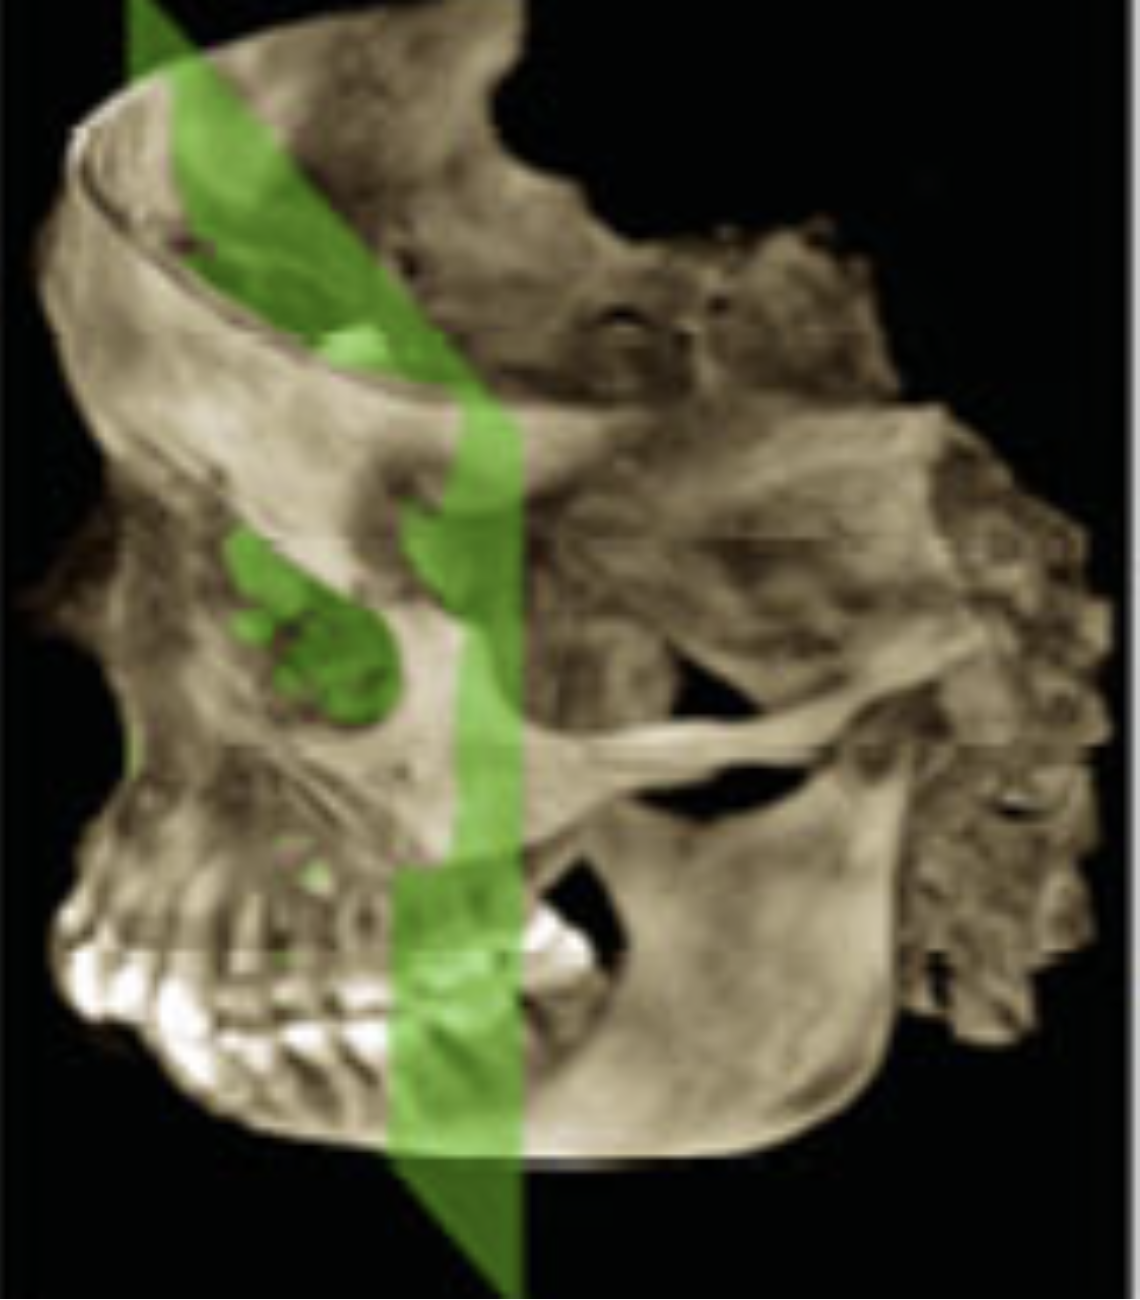

6

Q

What view?

A

3D